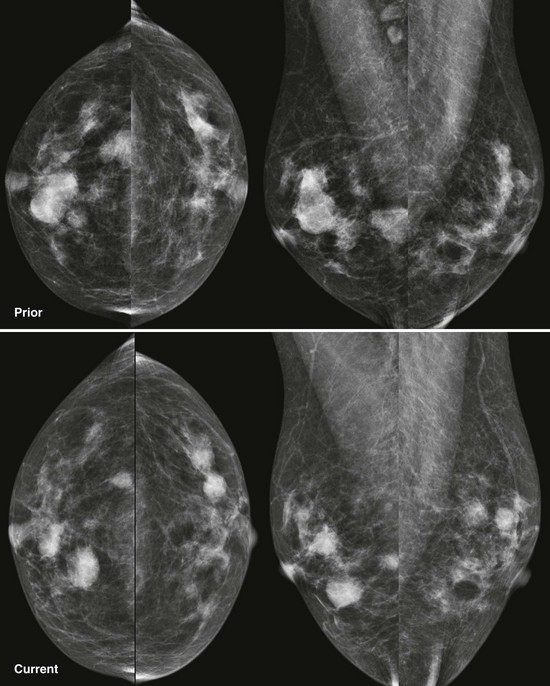

FIGURE 8-9 Waxing and Waning Cysts.

Some masses have enlarged while some have decreased in size. As long as the masses all have benign features and none are dramatically larger, recall is not necessary. This is BI-RADS 2.